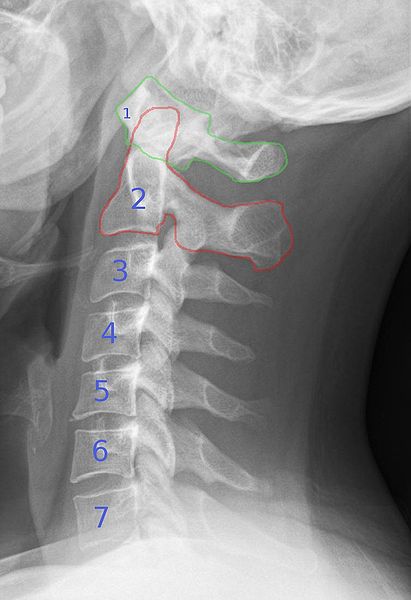

※私のレントゲンじゃありません

先生がレントゲンを診ると

「ああ、ここトゲになっている」

と一目瞭然との説明

よく解らなかったので、詳しく教えてもらうと

頸椎の5番と6番の形が台形になっておらず

変形しているとレントゲン写真を指して教えてくれた

それでもよく見えないので、顔を写真に近づけて

再度、説明を受けたところ、確かに形が違うことは判った